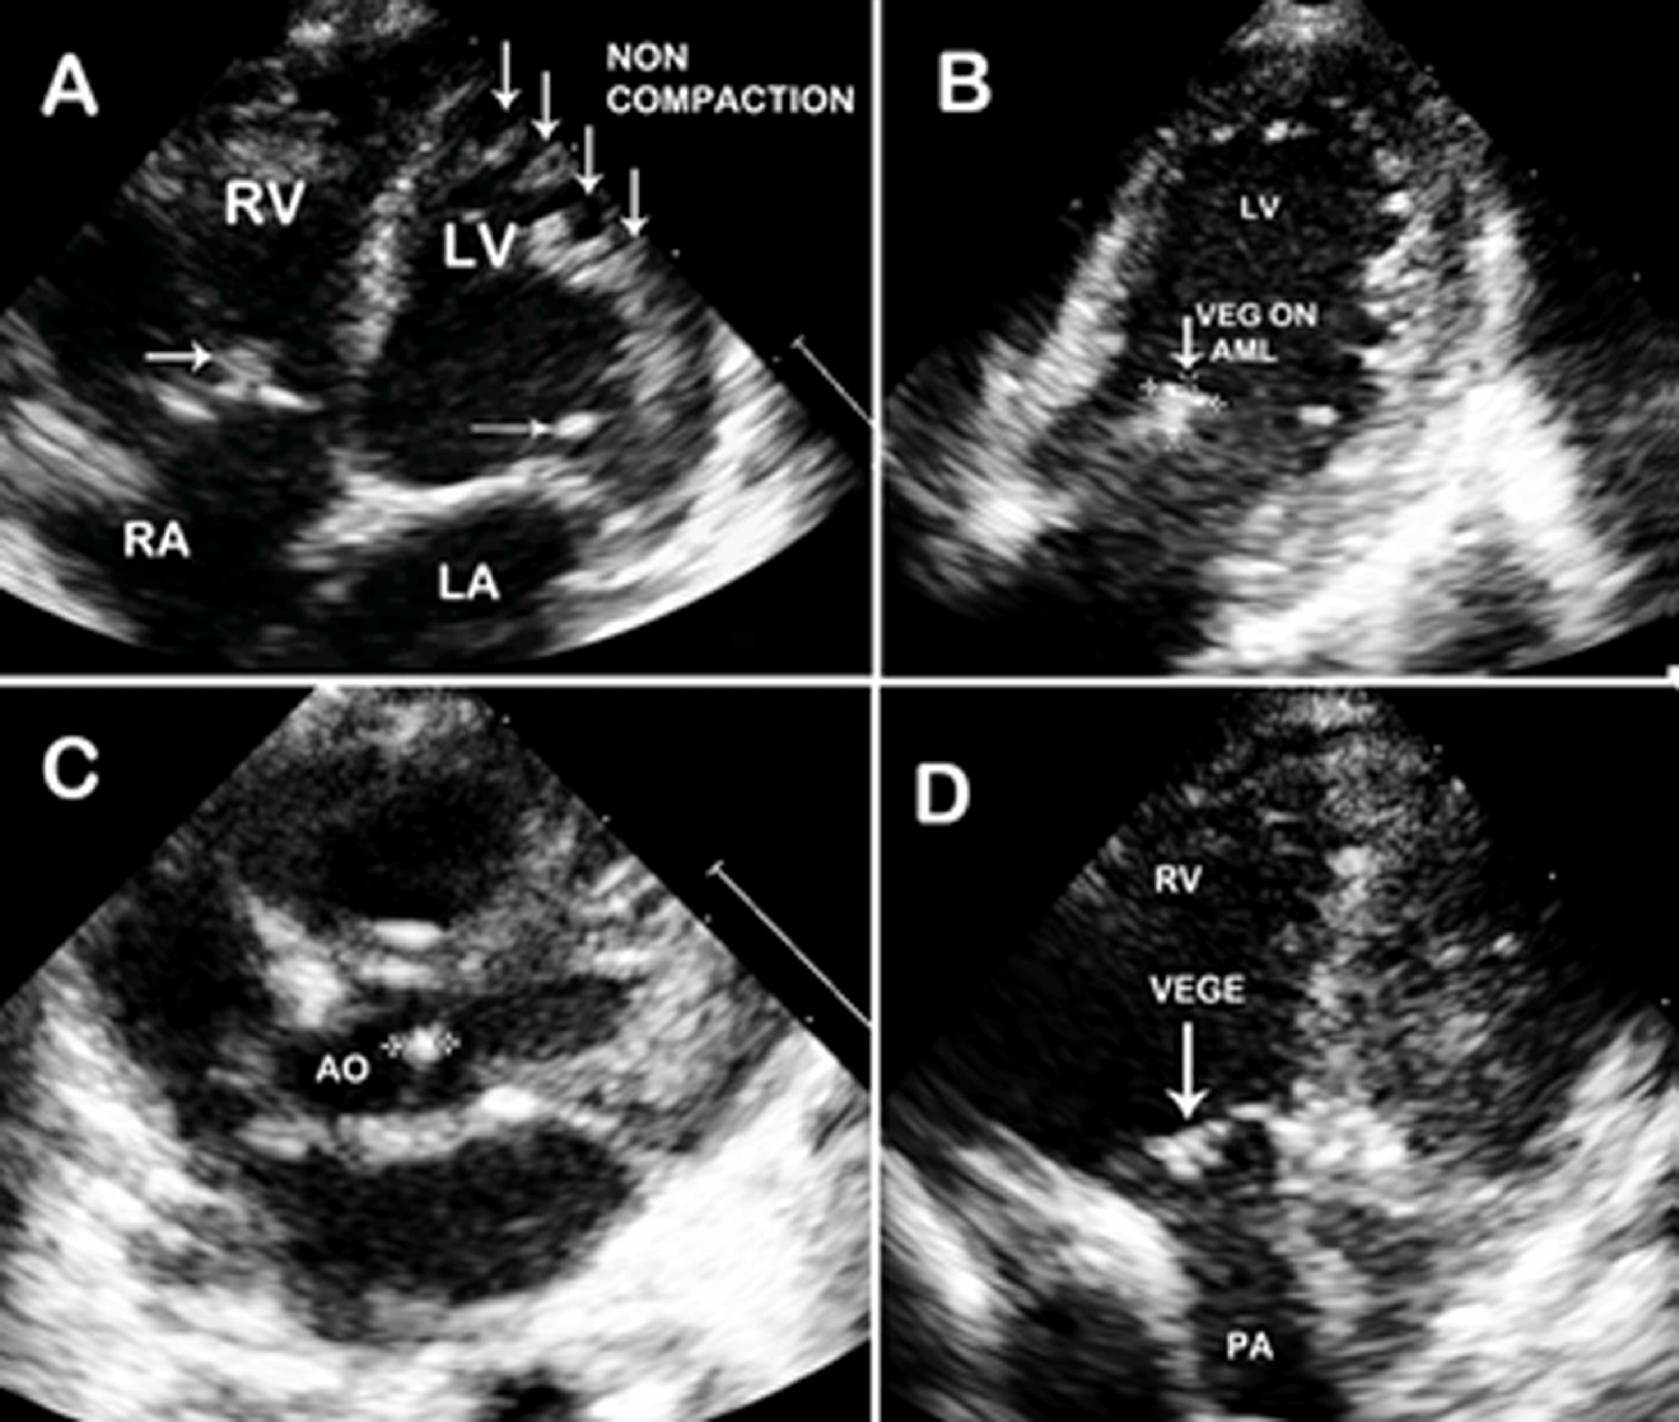

A 15 days old male neonate was referred with history of chest retractions, not maintaining oxygen saturation and feeding difficulties. This child was delivered by caesarian section at 36 weeks of gestation for premature rupture of membranes of two days duration. The birth weight was 3.15 kgs. The child developed sepsis, heart failure, acute tubular necrosis, hypoglycemia and hyperbilirubinemia. The transthoracic echocardiography (TTE) done at 15 days of age showed noncompaction of left ventricle with reduced function (EF-40%), pulmonary hypertension (50 mm Hg), multiple vegetations on all four valves (Figs. 1A,B,C,D) and multiple vascular channels in the left lobe of liver with both arterial and venous pattern, which was suggestive of vascular malformation. The CT angiogram of the abdomen showed 58x29x50 mm markedly enhancing lesion seen in relation to left lobe of liver suggestive of haemangioendothelioma. As per the blood culture report (Gram negative bacilli-Klebsiella) the neonate was treated with the antibiotics meropenam 100 mgs twice a day for three weeks and ceftriaxone 150 mg twice a day for four weeks.

Fig. 1A. Transthoracic 2D echocardiography in apical four chamber view shows vegetation on tricuspid valve and mitral valve with deep recesses due to LV non compaction. B: Modified two chamber view shows large vegetation on the anterior mitral leaflet. C: Short axis shows vegetation on aortic valve. D: Modified view shows multiple fuzzy echoes on pulmonary valve